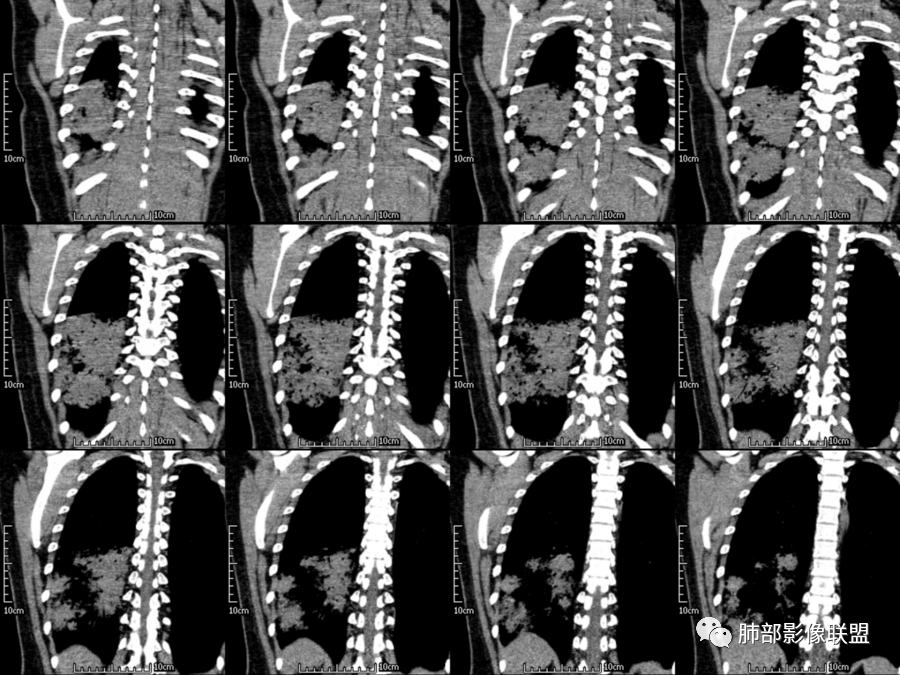

右肺胸膜下实变,病变跨多个叶生长,宽基底与胸膜相连,近端支气管穿行病灶内,并可见片状磨玻璃影,边界清,部分远端小支气管堵塞,支气管略有扩张,周围散发小结节,临床年轻女性,炎性指标高,发热六日,首先考虑感染性病变(肺链,奴卡,隐球,OP)鉴别淋巴瘤。

年轻女性,无明显诱因发热,体温略高,起病较急,有畏寒,右下肺紧贴胸膜下片状实变影,部分融合,外围有结节影,性质比较单一,类似于蘑菇兄弟,病灶周围伴有晕,支气管进入近端扩张远端堵塞,常规考虑感染,肺炎链球菌、隐球菌。

青年女性,发热咳嗽5天,炎症标志物升高。右肺下叶大片实变伴周围GGO,GGO内未见细网格,主体与胸膜平行,似多个病灶融合,实变区内见支气管部分进入,部分支气管受压狭窄,周围可见多发卫星病灶。支持炎性,考虑隐球感染,鉴别op。

年轻女性,急性起病,咳嗽,发热,黄痰,白细胞高,CRP基本正常,基础体健。CT提示右肺下叶实变,宽基底与胸膜相连,长轴平行于胸膜,可见支气管充气征,于病变中央截断,走形自然,胸膜下脂肪间隙可见,倾向于隐球菌,鉴别肺链,军团菌等。

年轻患者,右肺下叶大片状实变影,长轴与胸膜平行,内见含气支气管征,周围磨玻璃晕影。考虑感染性病变,隐球?

病灶长轴与胸膜平行,边缘有晕,病灶融合趋势,支气管进入,走行自如,考虑隐球菌肺炎。

年轻女性,急性发病,咳嗽咳痰五天,炎性指标升高,右肺下叶胸膜下大片实变影,周围见磨玻璃影,边界清晰,长轴与胸膜平行,呈融合趋势,支气管进入走行自然,远端截断,考虑炎性,隐球菌可能。

年轻女性,发热,急性发病,白细胞高,右肺下叶大片实变,长轴与胸膜平行,内见支气管走行,远端截断,周围有晕,晕边界清,考虑感染,隐球可能,鉴别淋巴瘤。

年轻女性,右肺下叶胸膜下多发实变、结节影,宽基底与胸膜相连,边缘模糊不清,实变内见支气管穿行,血象高,考虑感染性病变,大叶性肺炎?隐球?

青年女性,发热咳嗽急性起病,右肺下叶大片状实变密度影,长轴平行于胸膜,边缘模糊可见磨玻璃影及高密度结节影,实变内可见支气管穿行,直达病灶远端,考虑感染性病变,隐球菌可能大。

右肺胸膜下实变,病变跨多个叶生长,相互融合,宽基底与胸膜相连,支气管气象,并可见片状磨玻璃影,边界清,炎性指标高,发热六日,考虑感染病变,链球菌?腺病毒待排。

右肺下叶大片状实变影,长轴平行于胸膜,边缘模糊可见磨玻璃影,支气管进入,部分近端阻塞,考虑感染性病变,隐球菌,鉴别大叶性肺炎。

年轻女性,起病急,白细胞,C反高,存在感染。右下肺大片实变影,支气管充气征,长轴平行胸膜,似多个病灶融合,周围GGO,部分清,部分不清。考虑感染,隐球可能。

青年人,右肺多发团片状阴影,边缘模糊,周围可见磨玻璃影,内部有支气管空气征,考虑感染性病变,隐球菌感染可能。

右肺下叶大片状实变影,从外向内,长轴平行于胸膜,边缘模糊,可见磨玻璃影,支气管进入,远端部分阻塞,考虑感染性病变,隐球菌,鉴别淋巴瘤。

26岁,女性,发热、咳嗽5天。咳少量黄痰,起病急,病程短,白细胞及中性高,血沉及D-二聚体增高。胸部CT:右肺下叶大片实变,长轴沿胸膜分布,宽基底与胸膜接触,边界不清,周围GGO,部分团片影融合,病灶内可见支气管充气征,部分支气管进入病灶后阻塞。考虑:感染性病变,隐球菌?脓毒肺栓塞?鉴别:肺炎型肺Ca。

年轻女性,右肺下叶一大片实变影,似有多个结节影融合,周围有晕,内见支气管充气征,部分支气管进入后截断,病变近胸膜,长轴胸膜平行,考虑炎性,隐球菌首先考虑。

青年女性,影像表现右肺下叶胸膜下大片状实变影,近端见充气支气管征,边缘见片状磨玻璃影,下叶背段尚可见一结节。考虑感染性病变,隐球菌感染可能。

右下肺大片实变影,空气支气管征,边缘GGO,小叶间隔增厚,周围有蘑菇兄弟,基底宽,与胸膜平行,考虑隐球菌感染,鉴别肺炎型肺癌。

晨读:年轻女性,右肺胸膜下实变影,平行于胸膜,边缘磨玻璃影,内见支气管充气征,走形自然,略扩张。考虑感染性改变,隐球,肺链。2月发病,病毒性肺炎要考虑。鉴别淋巴瘤。

晨读:年轻女性,发热咳嗽5天。白细胞计数升高。右肺下叶大片状高密度影,边缘模糊,有实变 GGO,其内见支气管气相、无受压变细,无枯枝表现,其近端支气管无异常,右肺下叶背段见结节状影,定性考虑:炎症,隐球菌感染可能,炎症型肺癌不支持。

右下肺胸膜下大片状高密度影,其长轴与胸膜平行,病灶近端GGO模糊,部分支气管进入后阻断,支持感染性病变,考虑隐球菌